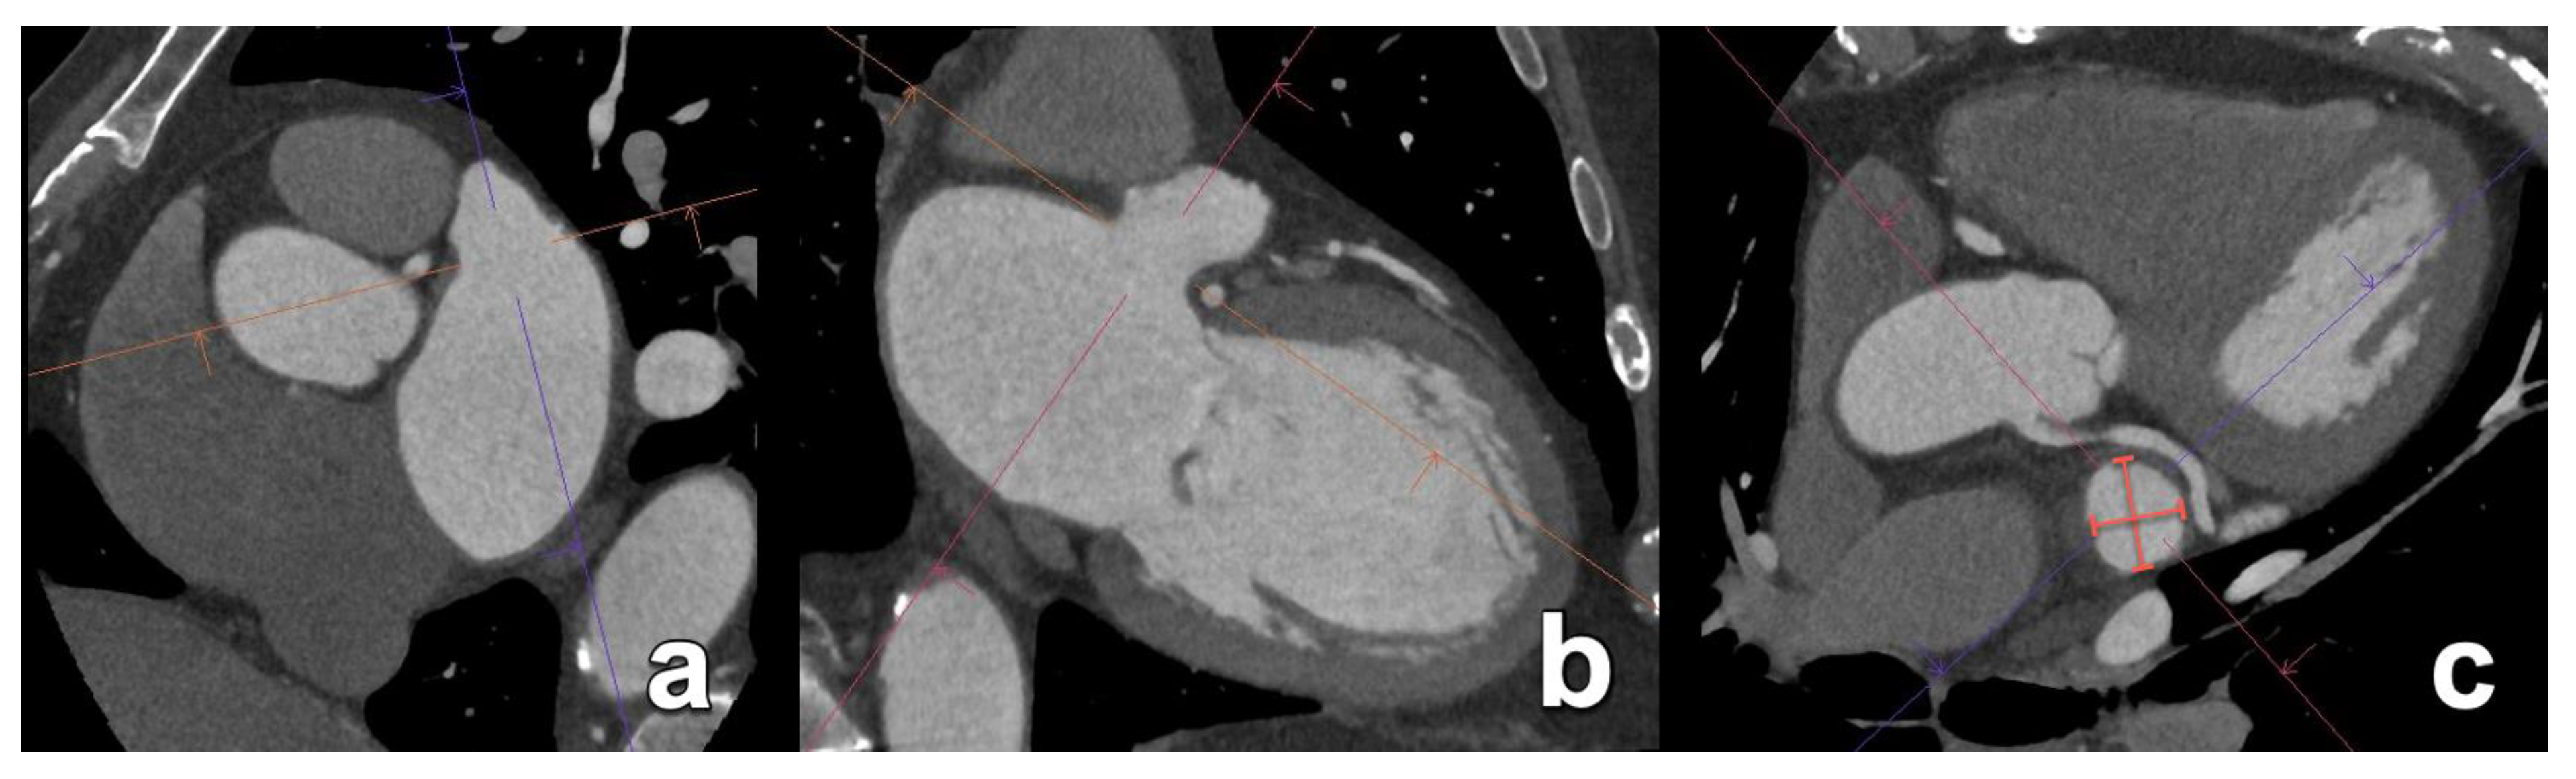

- Cronin, P.; Sneider, M.B.; Kazerooni, E.A.; Kelly, A.M.; Scharf, C.; Oral, H.; Morady, F. MDCT of the Left Atrium and Pulmonary Veins in Planning Radiofrequency Ablation for Atrial Fibrillation: A How-To Guide. Am. J. Roentgenol. 2004, 183, 767–778. [Google Scholar] [CrossRef]

- Lacomis, J.M.; Wigginton, W.; Fuhrman, C.; Schwartzman, D.; Armfield, D.R.; Pealer, K.M. Multi–Detector Row CT of the Left Atrium and Pulmonary Veins before Radio-frequency Catheter Ablation for Atrial Fibrillation. RadioGraphics 2003, 23, S35–S48. [Google Scholar] [CrossRef] [PubMed]

- Eifer, D.A.; Nguyen, E.T.; Thavendiranathan, P.; Hanneman, K. Diagnostic Accuracy of Sex-Specific Chest CT Measurements Compared With Cardiac MRI Findings in the Assessment of Cardiac Chamber Enlargement. Am. J. Roentgenol. 2018, 211, 993–999. [Google Scholar] [CrossRef] [PubMed]